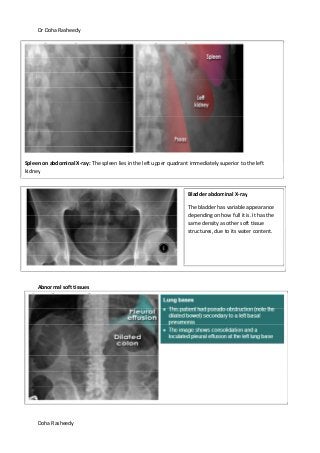

Abnormal soft tissues

Spleen on abdominal X-ray: The spleen lies in the left upper quadrant immediately superior to the left

kidney

Bladder abdominal X-ray

The bladder has variable appearance

depending on how full it is. It has the

same density as other soft tissue

structures, due to its water content.